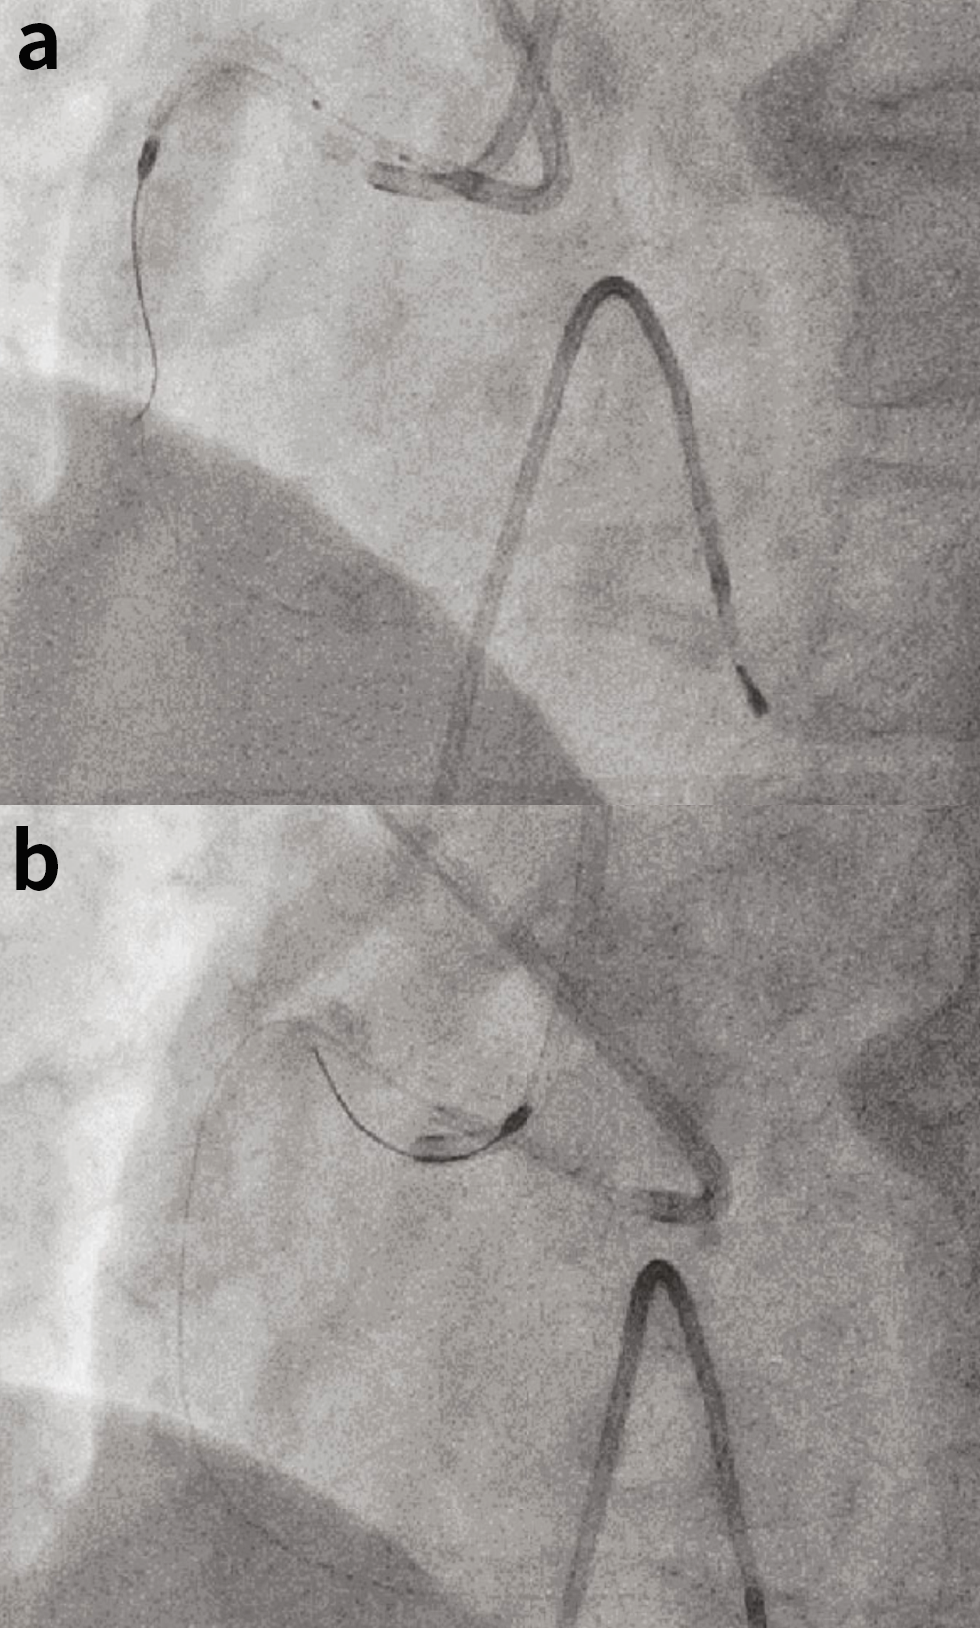

为了应对磨头杆断裂,在推进器附近切断了驱动轴护套、驱动轴和旋磨导丝,并将驱动轴护套拉出。尝试将圈套器推进至旋磨头处但未成功。沿着旋磨导丝将一根6Fr延长导管向磨头近端推进。然而,延长导管未能通过近端狭窄。因此,使用2.5mmNC球囊通过第二根引导导管对RCA近端进行扩张,随后对旋磨头滞留部位进行扩张(图3(b))。然后,推进延长导管,直到其与磨头接触,并将它们及旋磨导丝一起拉出(图4(a)),成功取出磨头(图4(b))。最后,在RCA中部植入4.0/15mm支架,并使用药物球囊对RCA近端进行扩张,完成治疗(图2(a))。

从断裂处取出磨头大约花费了80分钟。患者在整个手术过程中血流动力学保持稳定,术后恢复顺利。于术后第二天出院。6个月随访显示,患者无心肌缺血证据。

图4. (a)推进延长导管,直到其头端接触到。然后将延长导管、旋磨导丝和磨头一起拉出。(b)成功将旋磨头拉入到指引导管中取出。